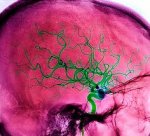

Инсульт это опасное и острое нарушение кровообращения в мозгу. Сегодня сосудистые заболевания находятся на втором месте в медицинской практике. Они очень опасны, так как не редко приводят к летальному исходу и способны изменить жизнь человека кардинально. Симптомы инсульта распознать очень сложно, но как правило его сопровождают головные боли, потери сознания, способности двигаться. Ведь мозг это